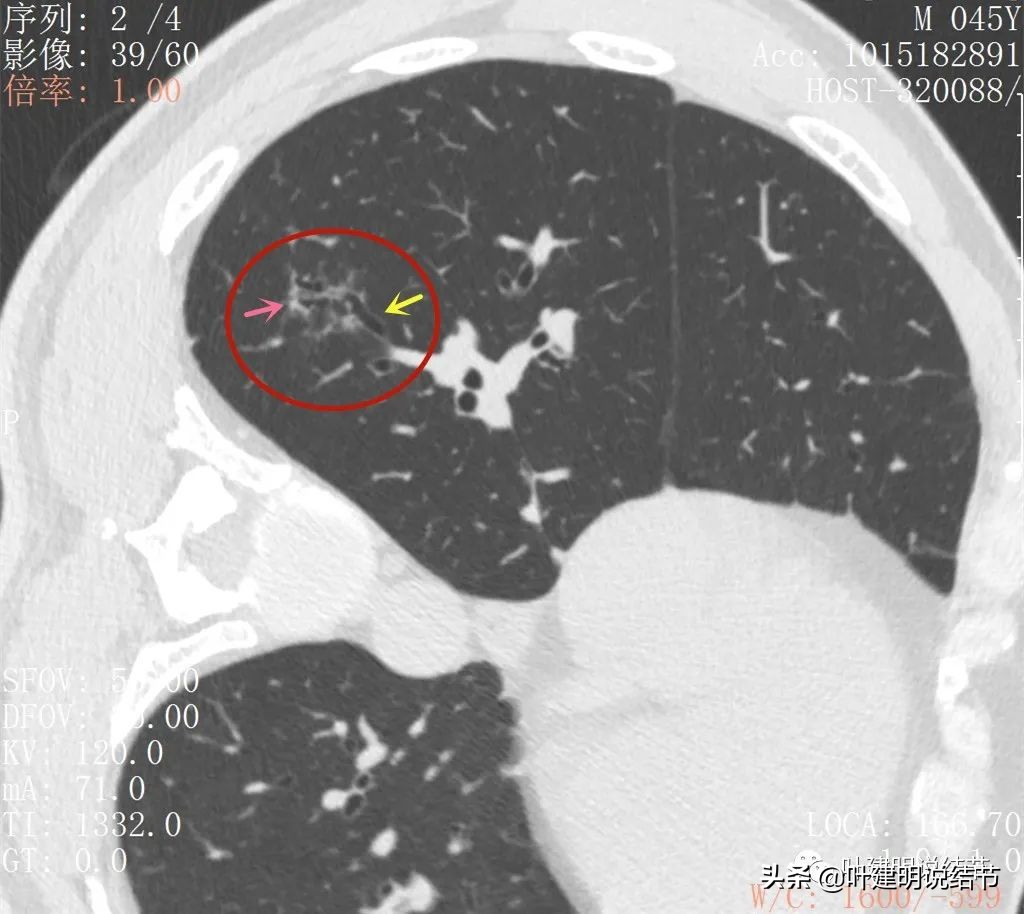

再来看薄层扫描:

病灶似乎非圆形或类圆形,扩张的细支气管壁密度偏高(蓝色箭头),感觉比较僵硬(黄色箭头),病灶轮廓显模糊(黄色箭头)

扩张细支气管壁密度较高,病灶轮廓显糊